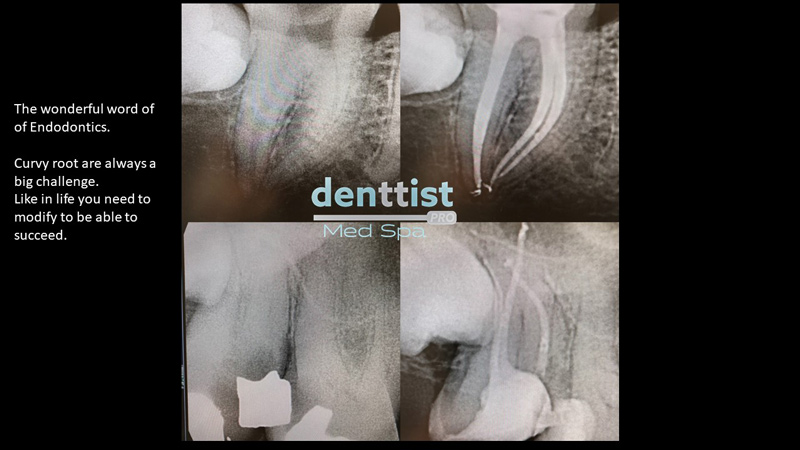

Tratamiento de Endodoncia